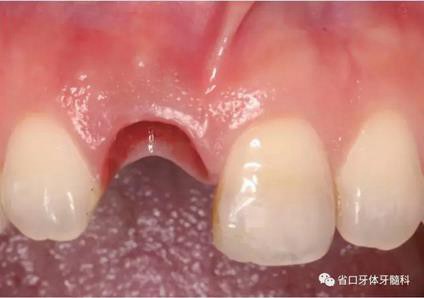

圖1 術(shù)前口內(nèi)照

圖2 術(shù)前口內(nèi)照

圖3 術(shù)前口內(nèi)照

(1)微創(chuàng)拔牙及即刻種植:術(shù)前拍攝口內(nèi)照及實(shí)施牙周基礎(chǔ)治療。常 規(guī)消毒鋪巾阿替卡因局麻下微創(chuàng)拔除上頜右側(cè)中切牙,搔刮拔牙窩及根尖肉 芽組織。探測(cè)牙槽骨唇側(cè)骨壁及鄰面牙槽嵴完整,牙齦無(wú)撕裂。不翻瓣下于上頜右側(cè)中切牙缺隙近遠(yuǎn)中中點(diǎn)的腭側(cè)牙槽骨及根方定位,按照逐級(jí)預(yù)備的原則,緊貼牙槽窩腭側(cè)骨壁制備種植窩洞,植入Zimer®3.7mm×13mm TSV種植體1顆,植入扭矩>35N·cm,以O(shè)sstell測(cè)量種植體的ISQ值為68。 種植體平臺(tái)位于唇側(cè)齦緣中點(diǎn)下3mm,與唇側(cè)骨壁內(nèi)側(cè)面形成的跳躍間 隙約2mm,置入Bio-Oss®細(xì)顆粒骨粉0.25g,上愈合基臺(tái)關(guān)閉創(chuàng)口。術(shù)后 CBCT檢查顯示:種植體利用牙槽窩根方骨質(zhì)固位,緊貼牙槽窩腭側(cè)骨壁, 其唇側(cè)面與牙槽窩唇側(cè)骨壁的內(nèi)側(cè)面所形成的跳躍間隙(約2mm)可見(jiàn)顆 粒狀顯影物充填。牙槽窩的唇側(cè)骨壁及唇側(cè)倒凹無(wú)缺損穿孔。